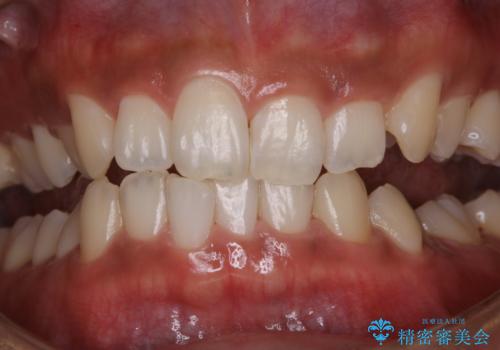

タバコによる着色をPMTCできれいな白い歯に

PMTCでは、歯の表面の凸凹にミネラルを補給して、ツルツルの表面に仕上げます。定期的にPMTCを行うことにより、歯質の強化になり着色がつきにくい状態になります。